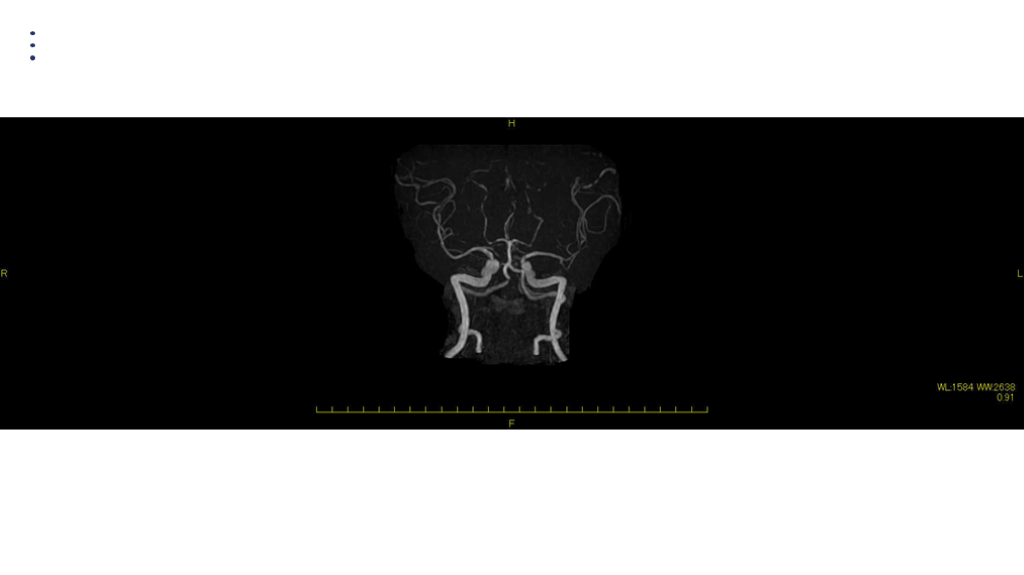

MRA DAY2

画像 所見 DAY 14 MRA 悪化